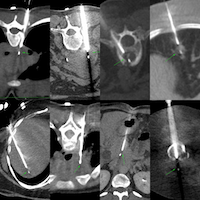

66-years old with treated lung cancer was found to have a right adrenal gland nodule.

Findings: Right adrenal gland nodule

Size of Lesion: 16 mm z axis x 12.4 mm

Gun: 18G BARD, long, 20 mm throw

No of cores: 3 for histopath

Position & Approach: left lateral decubitus - first prone, then rt lateral decubitus, then left plus hydrodissection, extrapleural

Time Taken (marker to wash-out): 17 mins

Complication: None

Level of Difficulty: 4/5

Diagnosis: Metastatic adenocarcinoma consistent with lung primary